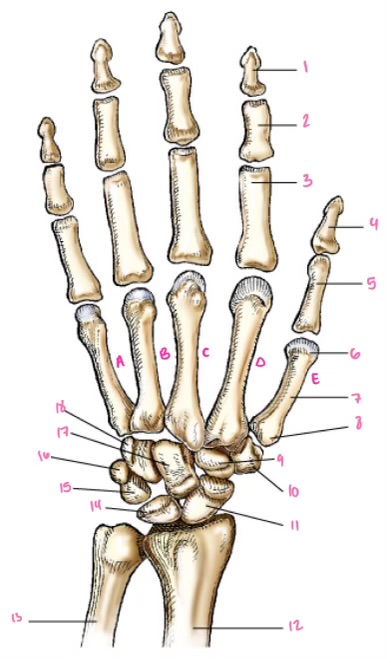

1

1

2

2

3

3

4

9

5

10

6

11

7

14

8

15

9

16

10

17

11

18

1

13

2

14

3

15

4

16

5

17

6

18

7

19

8

20

9

7

22

8

23

9

24

10

25

11

26

13

27

14

28

15

29

16

30

17